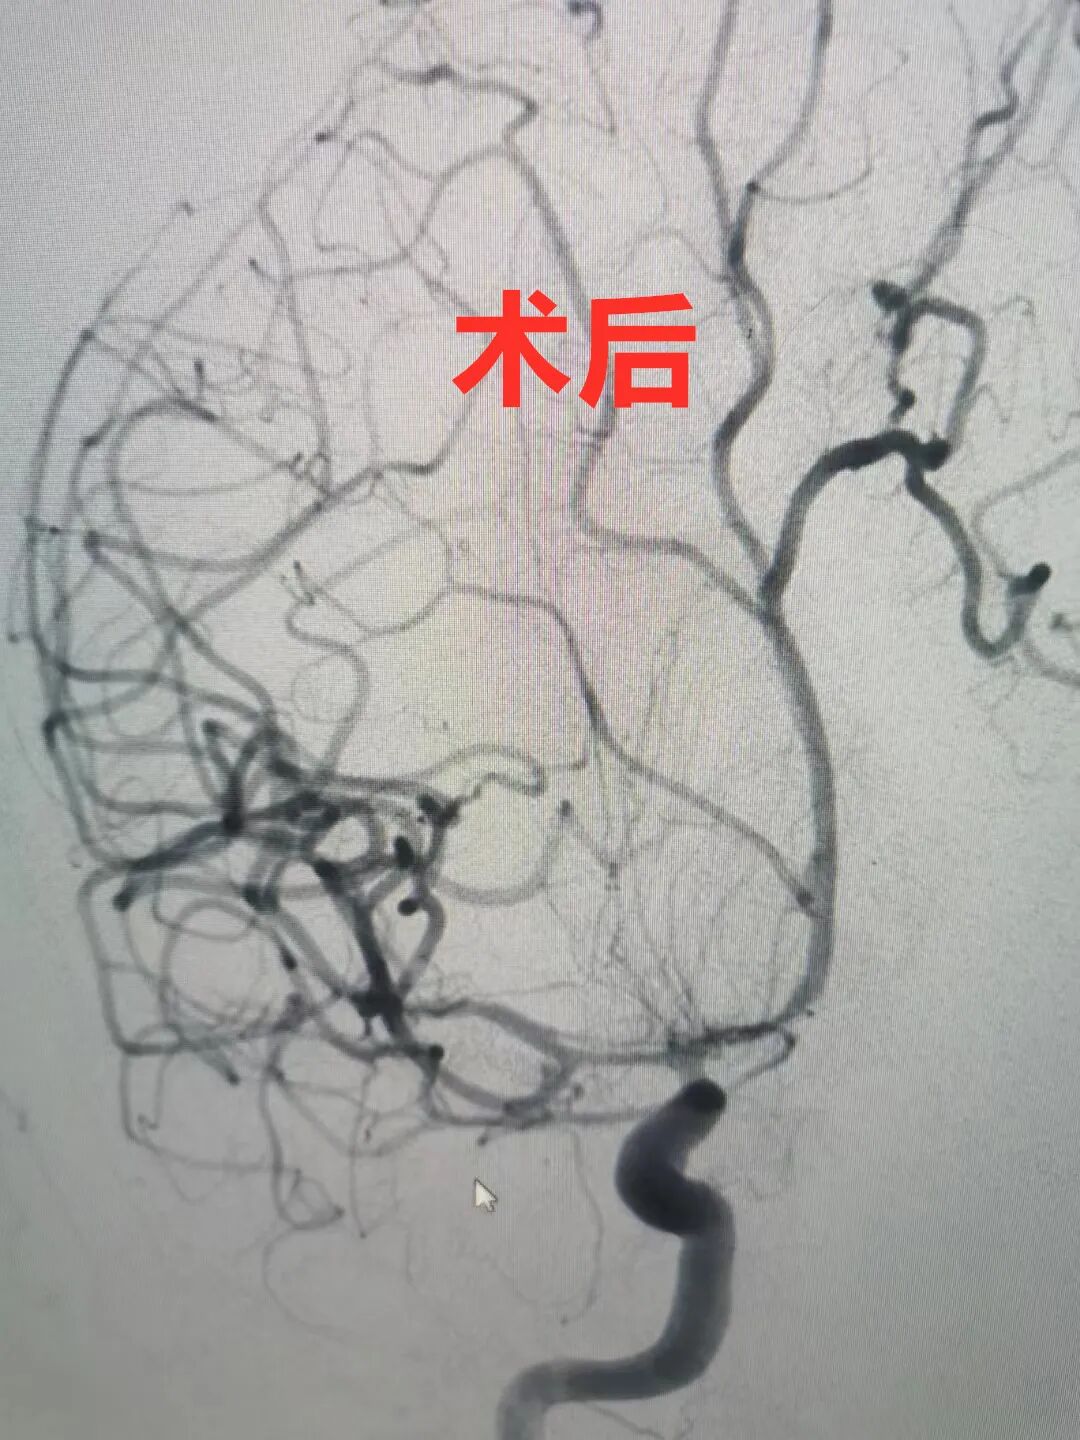

需要紧急进行“弹簧圈栓塞术

医院了解情况后,立即通过视频连线的方式和患者妻儿沟通病情,经家属同意手术后,迅速开展手术,与“死神”抢时间,经全力救治,确保了患者手术的成功。

19日医生查房时,何某精神甚佳与家属视频连线时,家属很满意并连声感谢:“你们河南人真好,新密人真有温度,非常感谢中康医院”!